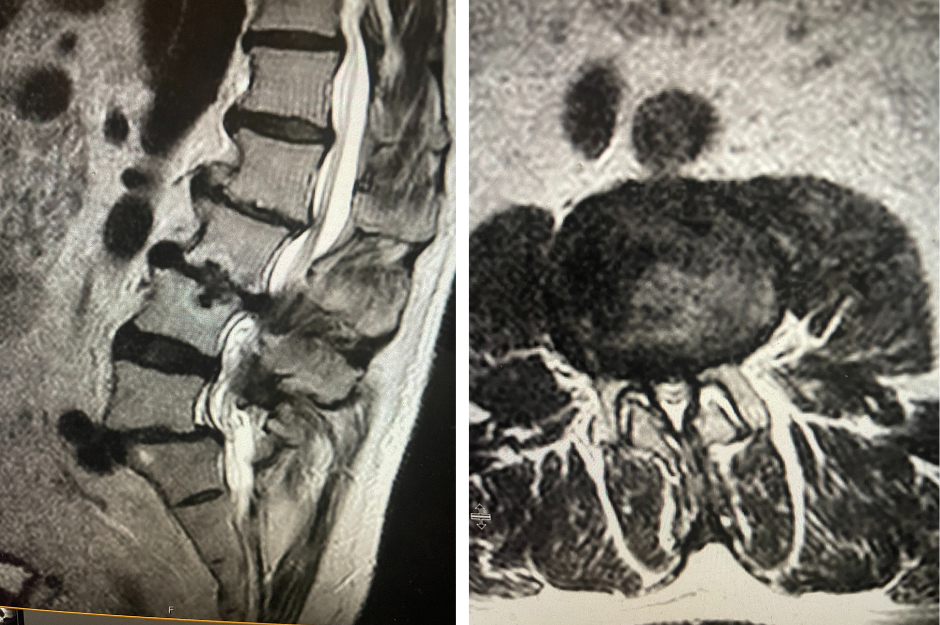

Figure 1. AP lumbar x-ray demonstrating degenerative lumbar levoscoliosis with secondary arthritic changes.

Figure 2. T2-weighted sagittal and axial MRIs demonstrating severe L3-4 stenosis and an L5-S1 grade 1 spondylolisthesis and spondylolysis and L3-4 retrolisthesis. Note the anterior osteophyte formation at L2-3 with attempted autostabilization of segment.

He had mild proximal weakness of his hip flexors. He also had a history of diabetes, hypertension, and hypercholesterolemia. Imaging studies were obtained. Plain x-rays (Fig. 1) demonstrated a degenerative levoscoliosis with the apex of the curve at L2-3. Lumbar MRI (Fig. 2) showed severe degenerative disc disease with an L5-S1 grade 1 spondylolisthesis and a significant retrolisthesis at L3-4 with severe lumbar stenosis.